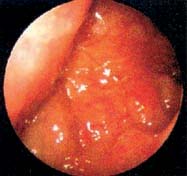

Εικόνα

1. Καρκίνωμα ρινοφάρυγγα, όπως φαίνεται με ενδοσκόπιο από τη μύτη.